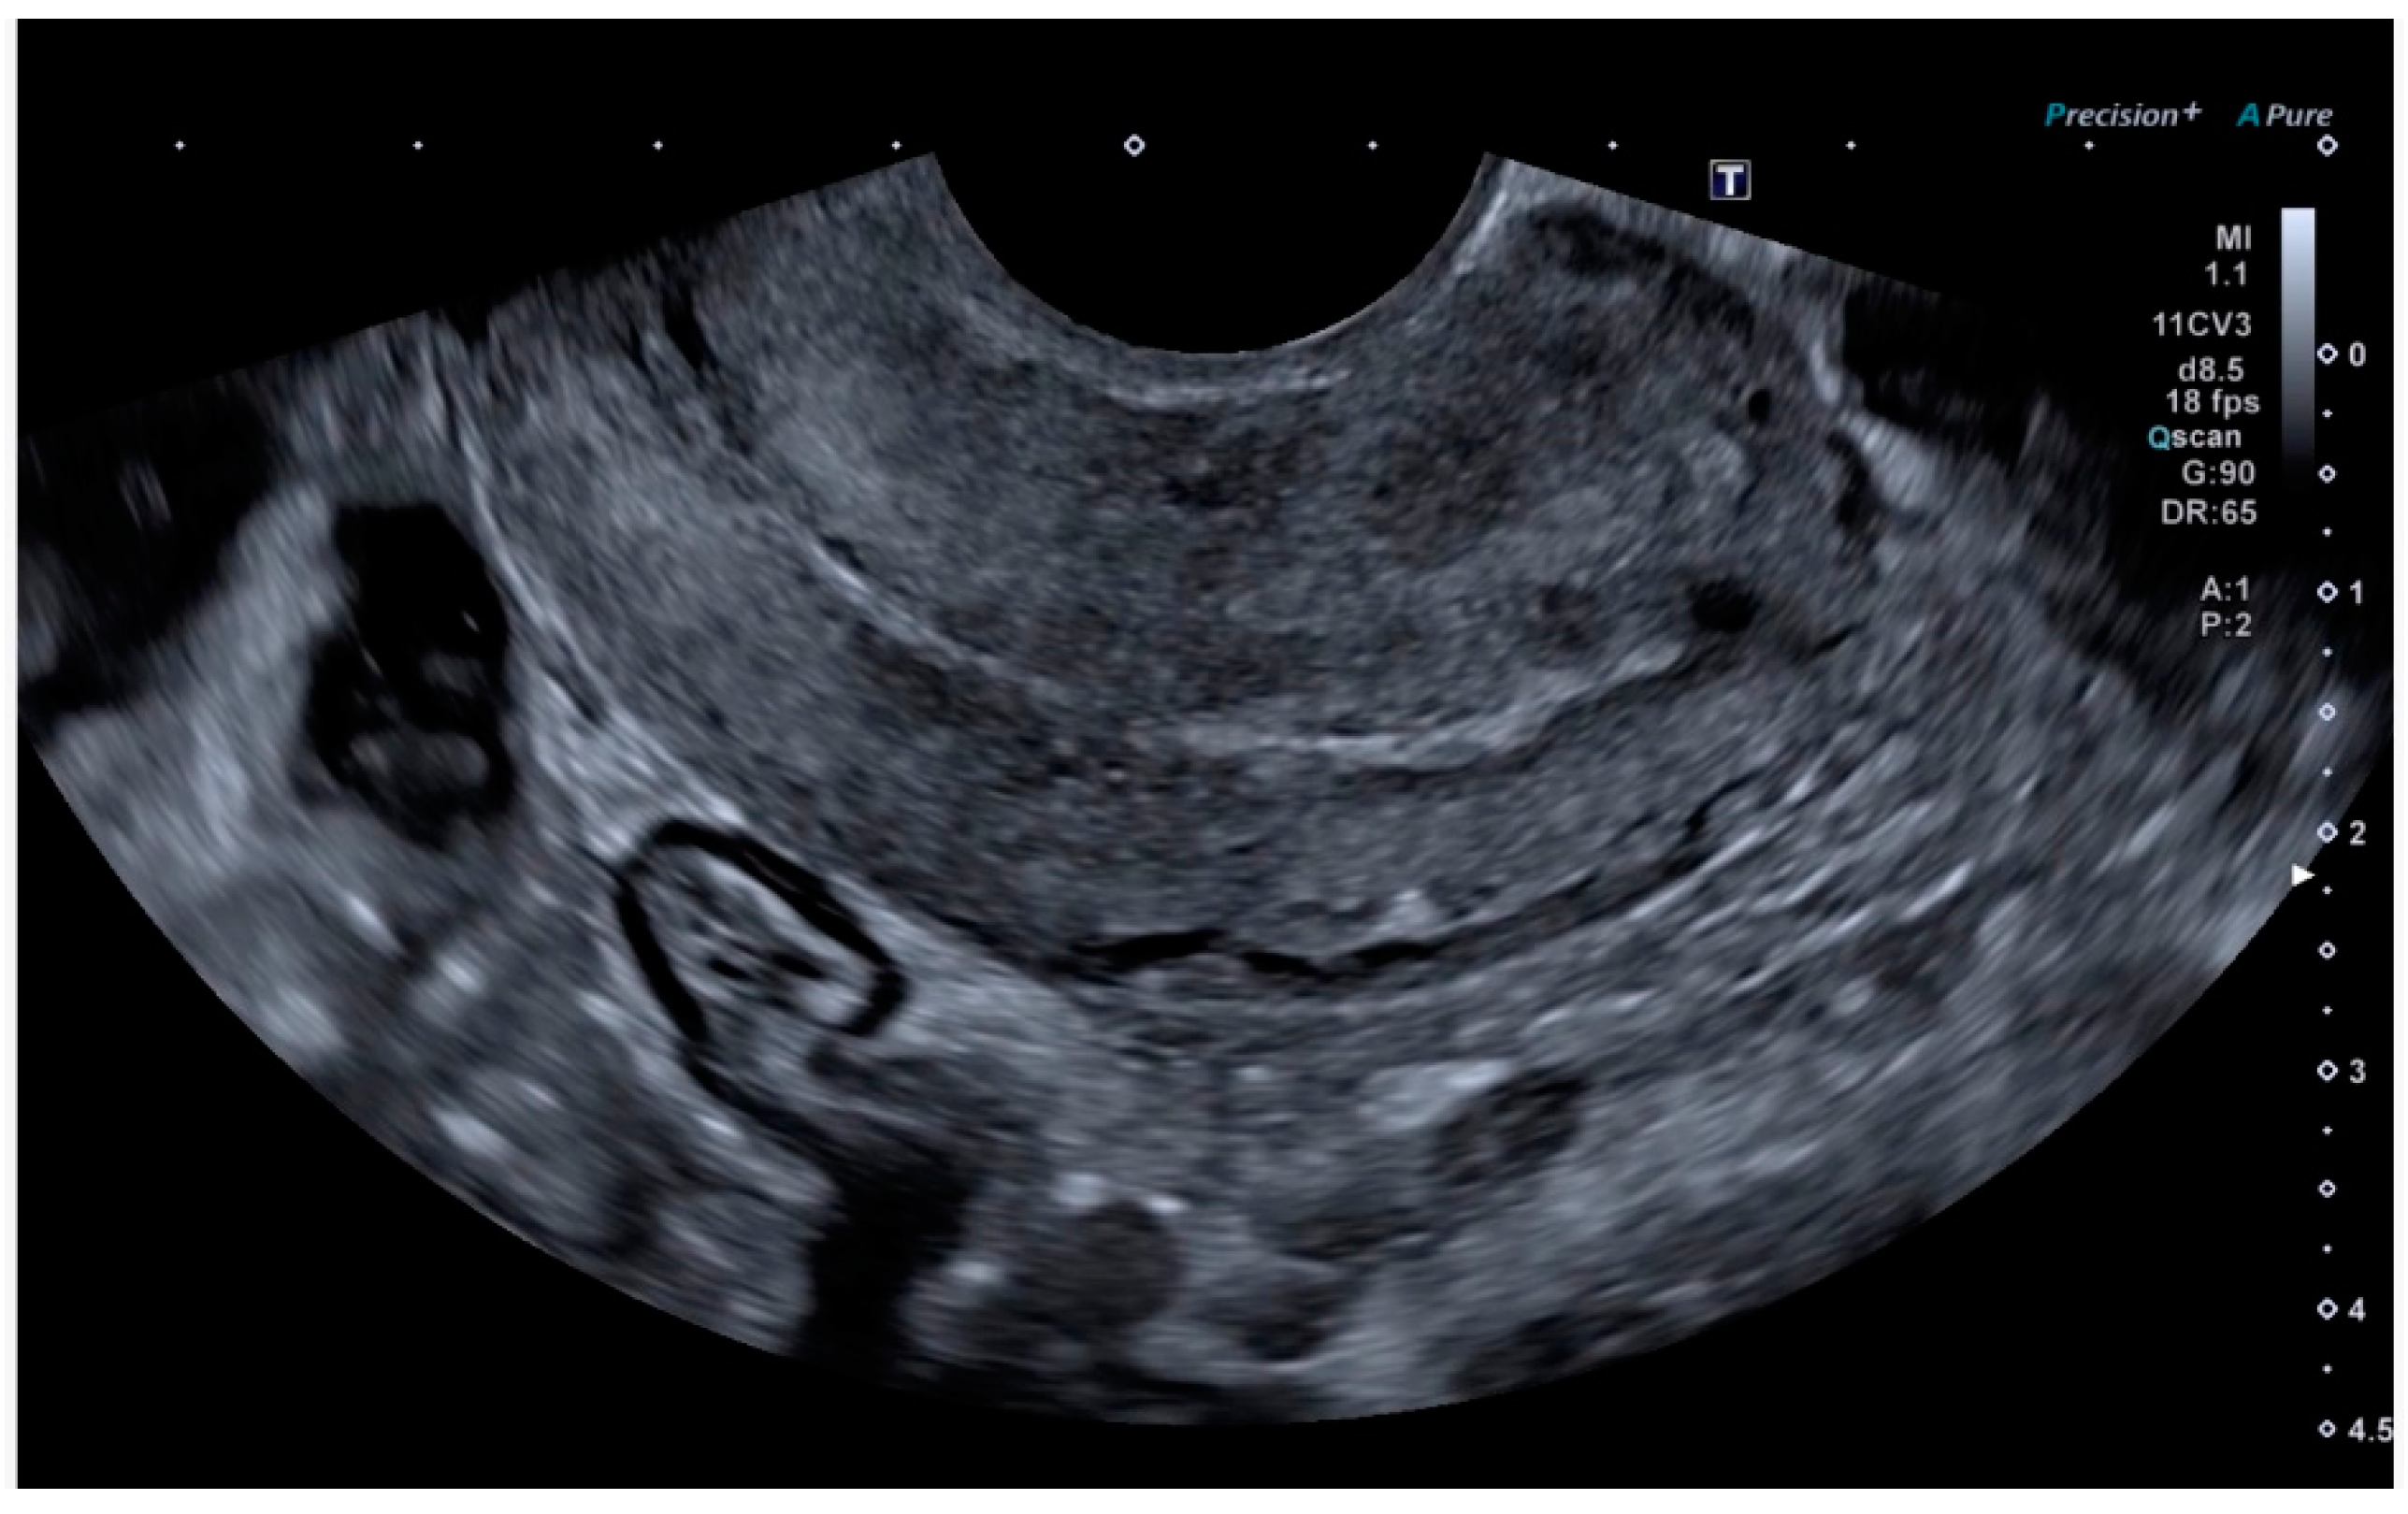

Finally, the vascular surgeons ruled out selective arterial embolisation because the size of the lesion made complete and effective embolisation impossible. Conservative treatment with combined hormonal contraceptives was chosen because the patient’s reproductive desires were not fulfilled. After four months of being asymptomatic and under treatment with combined hormonal contraceptives, the patient presented for follow-up, at which time no AVM was observed on the ultrasound, either in B-mode or colour Doppler (Figure 5 and Figure 6).

Figure 5. Linear endometrium after conservative treatment for 4 months.

Figure 6. Absence of colour Doppler uptake.